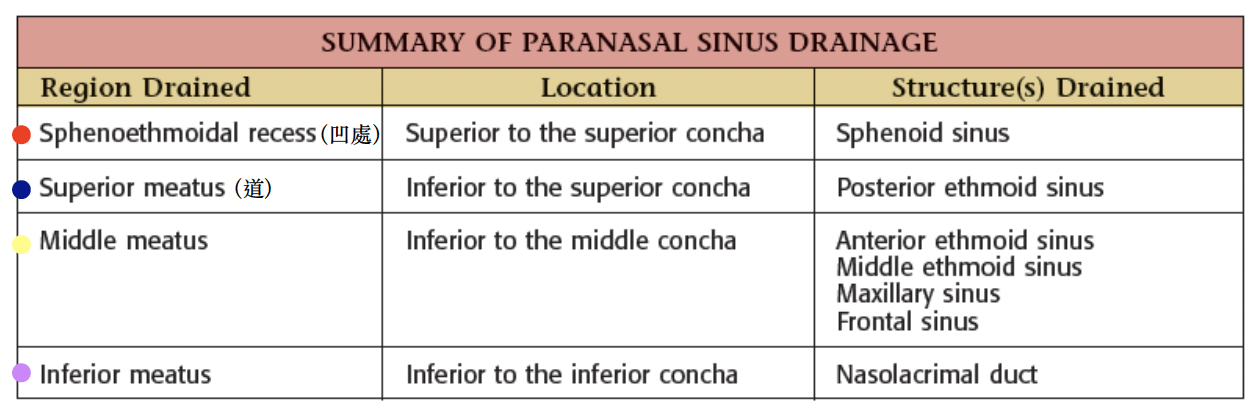

Paranasal sinuses

鼻旁竇,濕潤呼吸的空氣

Frontal sinus

神經皆CN V1

- Anterior ethmoid a.

- Supraorbital a./n.

- Supratrochlear (滑車上) a./n.

Maxillary sinus

來自Maxillary a. 3rd Part, Maxillary division

- Ant./mid. sup. alveolar a./n.

- Post. sup. alveolar a./n.

Ethmoid sinus

ethmoid bulla

Mid. ethmoid sinus 開口

Sphenoid sinus